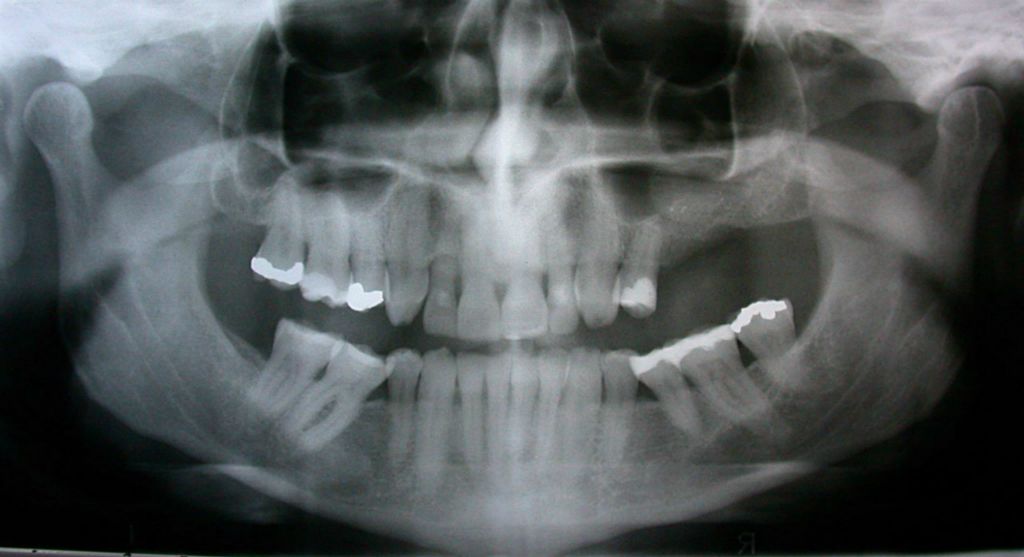

Before